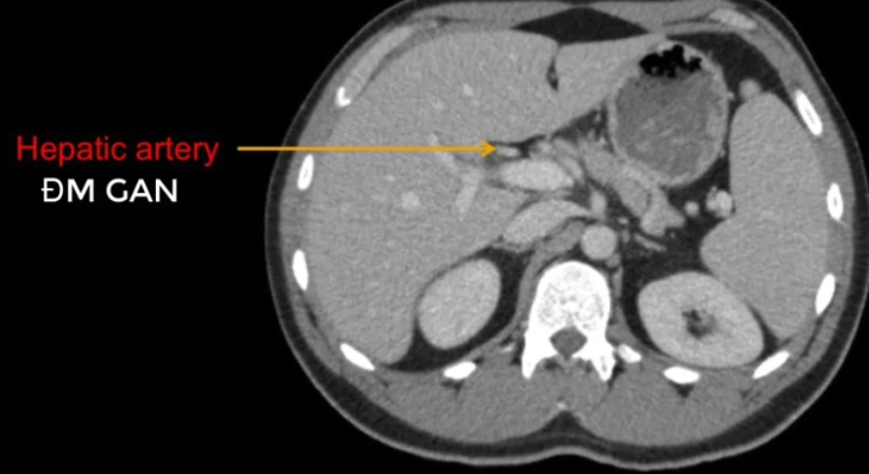

TM gan ở đâu? TM chủ dưới ? ĐM chủ?